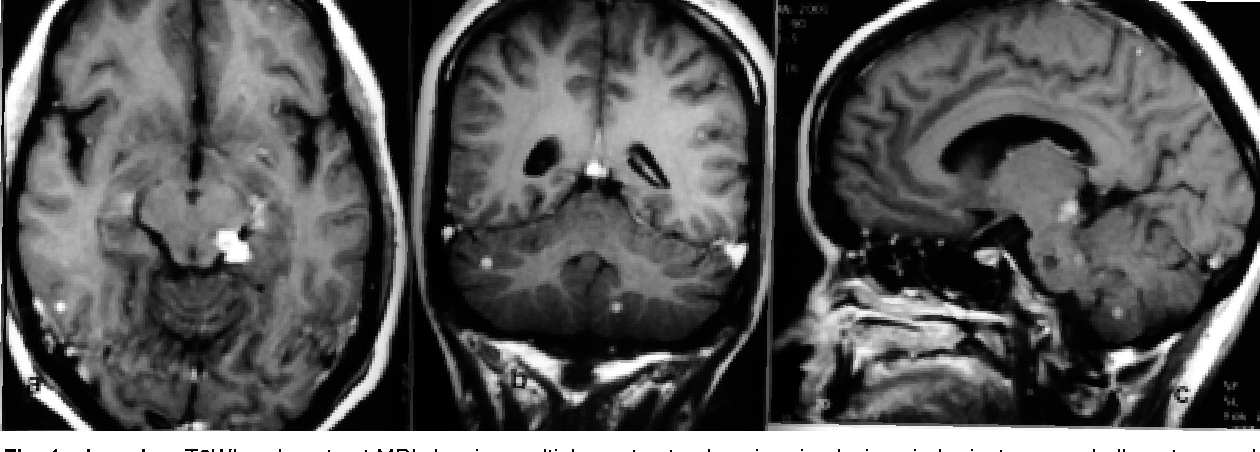

The causative agent of primary amebic meningoencephalitis is Naegleria fowleri. The humans get the amoeba from freshwater sources such as river and lakes. The amoeba enters through the nose to reach the brain where it causes infection. The condition is misdiagnosed as bacterial meningitis due to similar sign and symptoms. The signs and symptoms of primary amebic meningitis occur in two different stages. During the first stage, the following signs and symptoms appear: - Fever - Nausea - Vomiting - Frontal headache The second stage of primary amebic meningoencephalitis is characterized by: - Neck stiffness - Hallucinations - Seizures - Altered mentation - Coma Reference: https://www.cdc.gov/parasites/naegleria/illness.html Image via: https://www.semanticscholar.org/paper/Naegleria-meningitis%3A-a-rare-survival.-Jain-Prabhakar/e9db3c80a39329e64c831b965530c13d2a7fee1c/figure/0